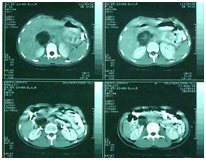

A 23 year-Old Iranian female patient presented with a six months history of fever, chest and abdominal pain, loss of appetite, weight loss, cough, night sweating and dyspnea was referred to our hospital. Physical examination revealed fever (39 centigrade), blood pressure 110/60 and coarse crackles at middle and lower area of both lungs. Abdomen was soft but a budging was seen in lower abdomen near the suprapubic region. Others organ, upper and lower extremity was normal. There was bilateral multiple nodular lesions at his chest X-ray. In hospital she takes ceftriaxone 2Gr and clindamycin 600mg twice daily. US of abdomen and pelvic was obtained and showed a cystic–solid lesion in the pelvic and in the liver. Computed tomography (CT) scan of the chest, abdomen and pelvic with IV contrast was obtained and showed multiple cavitary and solid-cystic mass lesions was showed in both lungs and the size of lesions were various in diameter. The lesions were located in the central and peripheral zone of both lungs (Figure 1). The abdomen and pelvic CT–scan showed solid-cystic mass in the pelvic and liver Radiologist finding and differential diagnosis was inflammatory lesion as Wegener granuloma, septic emboli, sarcoidosis and pulmonary metastasis from ovarian malignancy (Figure 2). Two days after admission, fever dropped and general condition of the patient becomes better. All lab date was normal except (ESR=40(0–20mm/h.CRP=22(0–5mg/L), WBC=16000). Fibroptic bronchoscopy was performed. Endobronchial lesion was not observed and bronchial lavage was obtained, Pathology examination of the bronchial lavage was normal, all other biochemical tests (CEA, ACE, RF, CA-125, hydatid tests and rheumatological tests) were normal. Laparatomy was performed ,the pelvic mass was excised and mass was opened, laminated membrane of hydatid cyst was seen, the lesion of liver was aspirated and fluid was clear, the mass was opened carefully and laminated membrane was seen (Figure 3) (Figure 4). With left mini anterolateral thoracotomy at 4 thintercostal space, chest wall was opened multiple nodules was palpable the big one was resected as wedge resection, the specimen was opened, laminated membrane was exposed (Figure 5). Chest tube was inserted and chest wall was closed in layers. Second post operative day, Albendazole was started at a dose of 10mg/kg/day for three cycle of 28days with 14days interval. Pathologist’s repot was hydatid cyst of lung in all three specimens (Figure 5). Patient was discharged in good condition 5days postoperative in the six months follow -up time there was no increased the size of both pulmonary nodules.

Figure 1 CT scan of the chest Show bilateral multiple nodules at both lungand cavitation.

Figure 3 CT-scan of abdomen show a cystic-solid mass of liver.